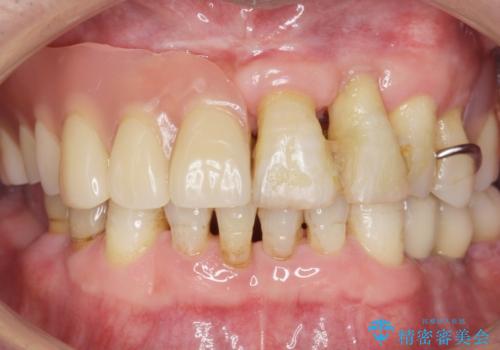

- 奥歯の違和感を主訴に来院された患者様です。

精査したところ、右下の奥歯は大きなう蝕により保存不可能な状態でした。

患者様のご希望により、抜歯後インプラント治療を行いました。

奥歯でしっかりと咬むことができるようになり、大変喜んで頂けました。